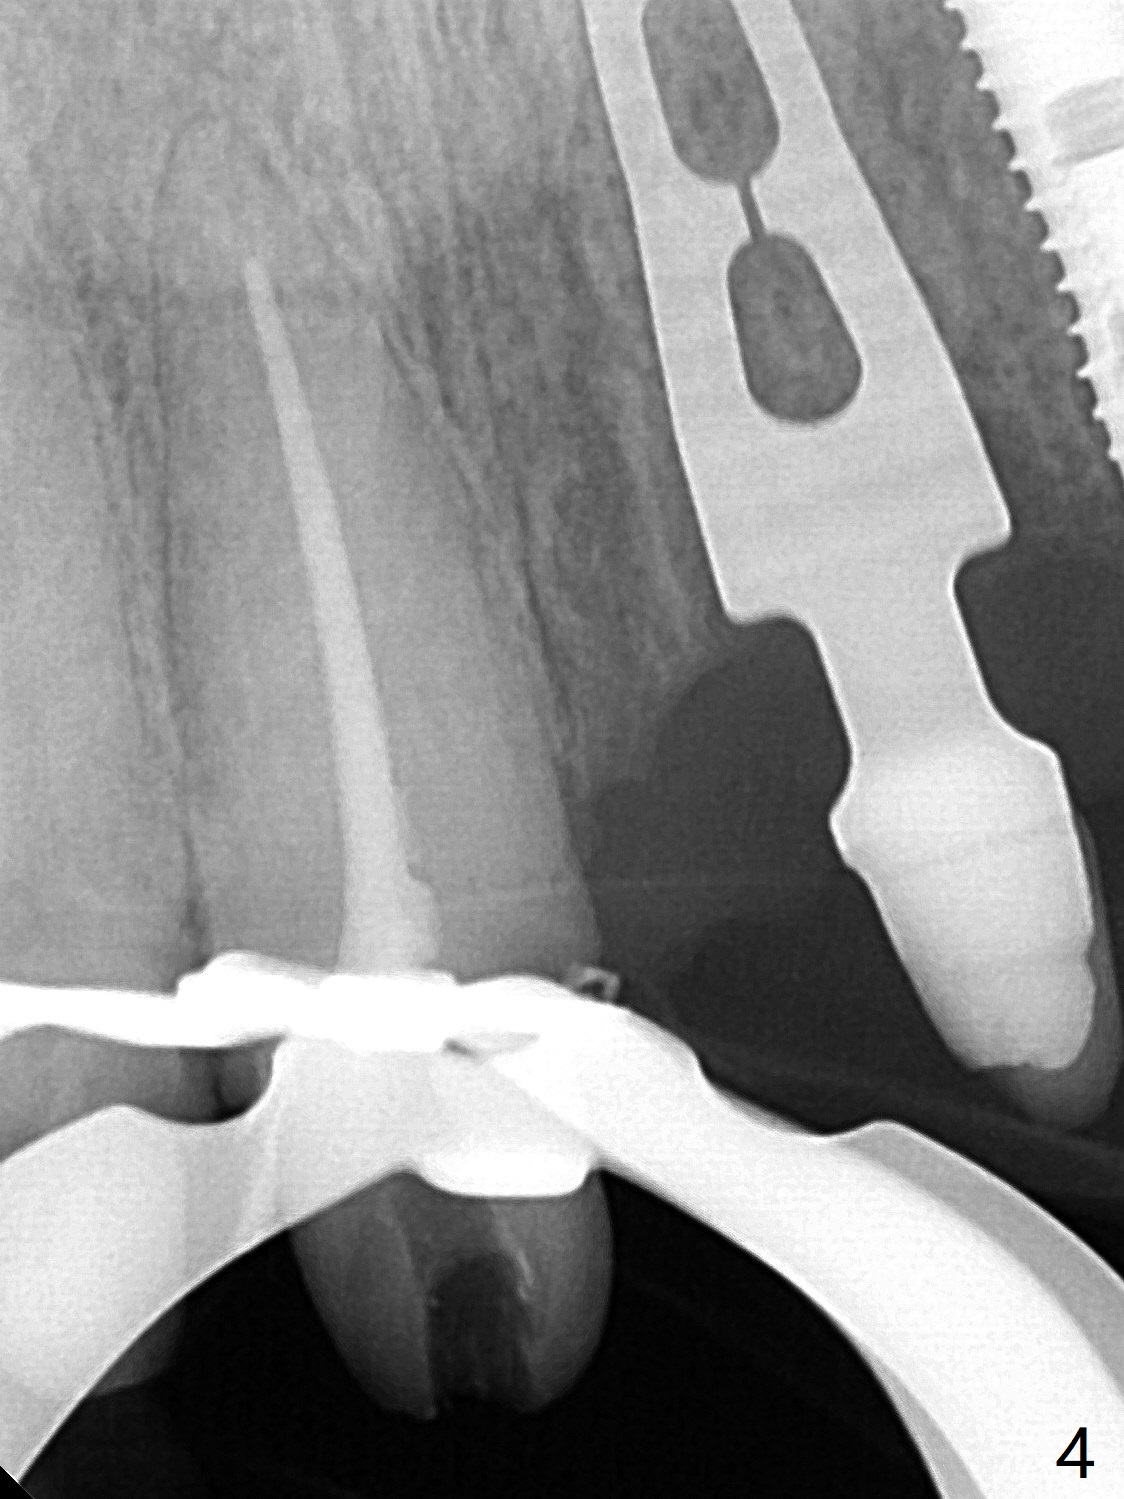

58岁女前牙桥撤除后三个月右上1(8号牙)出现牙髓炎,利用三个月前拍摄CT测定工作长度21.5毫米(图一),与术中根尖测定仪一致,但是40/.04 master cone没有达到工作长度(图二),再次使用根尖测定仪,工作长度22毫米,master cone空管临床上好像达到工作长度,但是加上糊剂,master cone临床上仍然不到工作长度,与根尖片一致(图三),三次切除牙胶尖,三次垂直压缩,仍然没有缓解长度问题(图四)。但愿临床上没有问题,此例是活髓。最终牙冠应用临时粘固剂。如果使用细的牙胶尖(考虑年龄因素),例如30/.04,可能简单些。